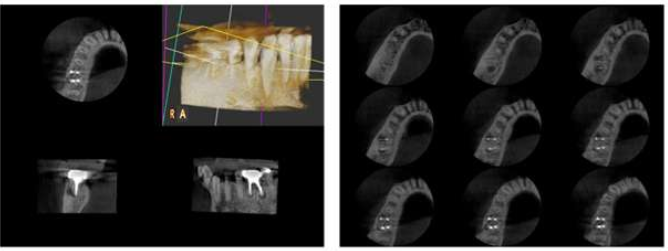

往復380度回転の撮影により、撮影範囲φ56mm×36mmの、より正確で歪みの少ない高解像度3D画像が得られます(オーラルモード)。日常の歯科治療から、歯内療法、シングルインプラントにおいても精細な部位の画像を取得することが可能です。

※デントモード:片道190度回転の撮影だけで撮影範囲φ30mm×36mmの、より正確で歪みの少ない高解像度画像が得られます。

スライス幅0.077mmを実現

断層撮影した画像を最薄0.077mmの幅でスライスすることができます。

0.077mmなので根管治療時の根管の形状・根尖・破折の確認や、外科的処置、埋伏歯の確認などが可能です。

根管治療

クリックで画像を拡大できます。

歯根の形態、根尖方向、破折だけでなく、根管充填の状況なども把握できます。

根尖病巣の大きさや形状についても把握もできます。